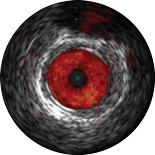

ChromaFlo provides easy assessment of stent apposition, lumen size and more by highlighting blood flow red at the touch of a button. ChromaFlo is available on Philips imaging systems.

Designed to make lumen size and stent apposition instantly recognizable and help identify branches, dissections, thrombus, and plaque distribution in bifurcations. ChromaFlo highlights blood flow red to identify:

No flushing and no special procedures are required during imaging. Simply activate ChromaFlo with a click.

ChromaFlo works with the Philips Eagle Eye Platinum digital IVUS catheters.